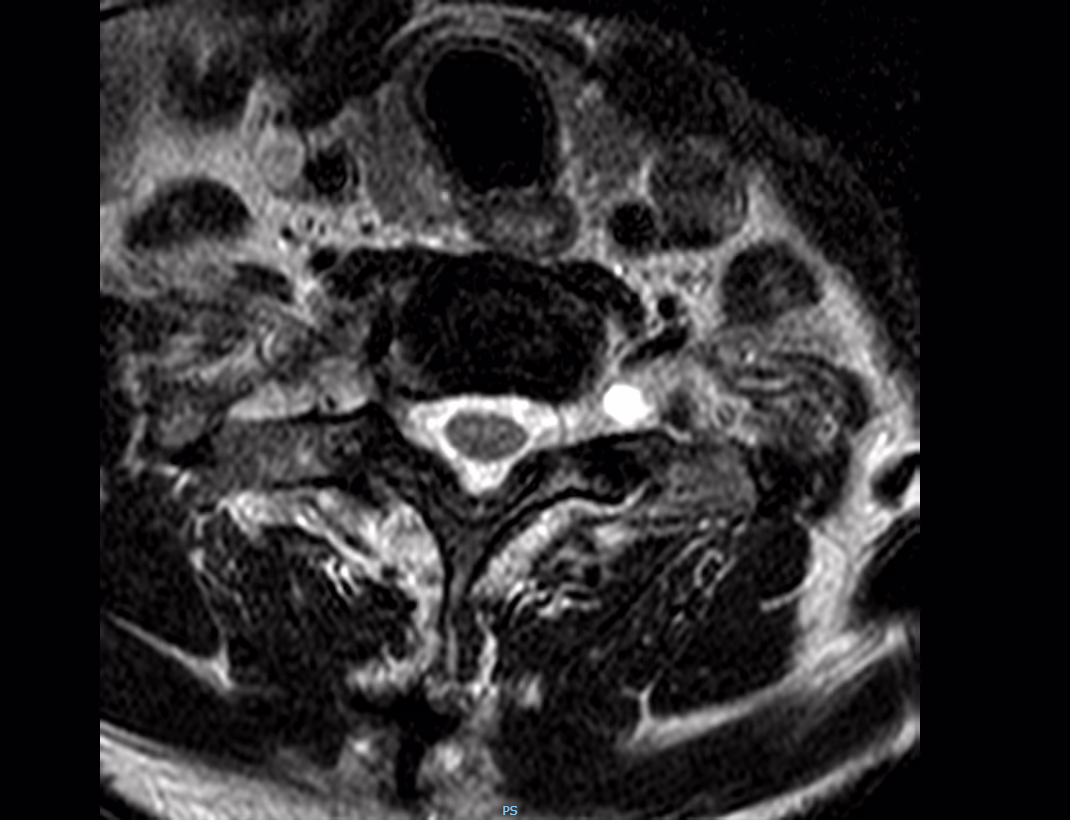

A nivel de espacio C6-C7 se tiene complejo disco-oseofitario con obliteracion del espacio subaracnoideo anterior

Los agujeros de conjunción con obliteración parcial a nivel de C3-C4 bilateral , y C6-C7 derecho

Como hallazgo adicional se tiene pequeño quiste perineural a nivel del agujero de conjuncion C7-T1